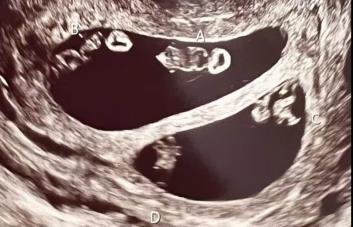

Una ugandesa de 70 años dio a luz a gemelos, convirtiéndose así en la madre más longeva de África, declaró el jueves a la AFP su médico.

Safina Namukwaya tachó de "milagro" el nacimiento de sus gemelos el miércoles en un centro médico de la capital, Kampala, donde había recibido un tratamiento de fertilidad.

Añadió que la madre y los bebés, una niña y un niño, siguen en observación, pero están en buen estado de salud.